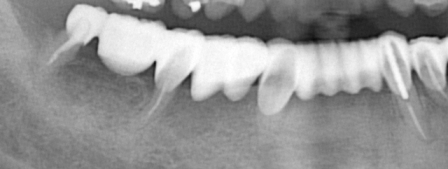

過重負担のブリッジ

右下 7 番(第二大臼歯)から左下 3 番(犬歯)までの 10 本の歯を 4 本の根でささえています。このような場合、完全に支える根の強度不足により、歯根破折あるいは根周囲の骨吸収が急激に生じる(咬合性外傷)可能性があります。